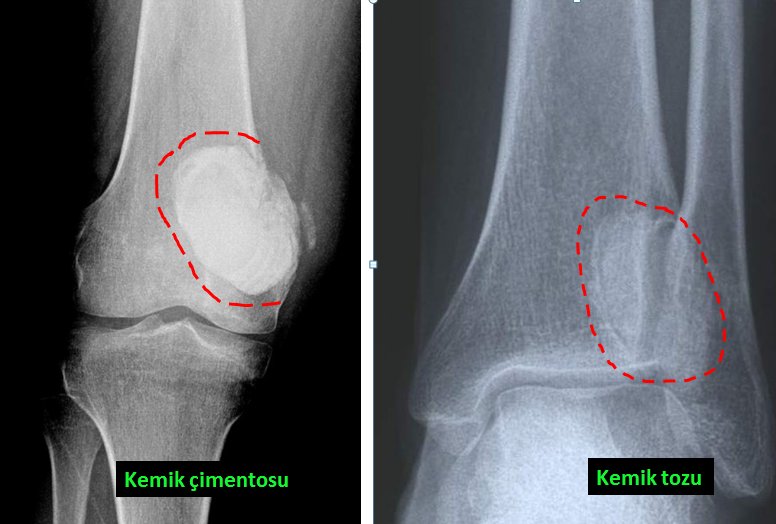

Benign bone tumors are mostly bone cysts, some tumors of cartilage origin or some lesions such as giant cell bone tumors. Cysts can be simple or complex. Simple bone cysts are more common in children. Although the most common area is around the shoulder, it can occur in any bone (picture-5). In the treatment of simple bone cyst, surgery is required in some cases, and sometimes non-surgical treatment can be applied. For this, the patient is injected into the cyst under operating room conditions and it may be necessary to repeat this several times (pic-6). What is meant by complex cyst is “aneurysmal” bone cyst. The treatment for this is only surgical, and after the cyst is cleaned, it should be treated with a number of special substances. The resulting cavity is filled with bone cement or bone powders (pic-7). Aneurysmal bone cyst is a more aggressive lesion than simple bone cyst and sometimes it can completely remove the bone. There is also a higher chance of recurrence.

Giant cell bone tumor is also more common in young people. Although this type of tumor is mostly seen in the knee, it occurs in all parts of the body, especially in the joint areas (picture-10). It is usually in the form of blunt pain felt in the last few months. It can only be treated with surgery. The tumor is completely removed from the bone and the cavity is filled with bone cement or bone powders (pic-11). If the removal of the tumor is not done completely, recurrence is inevitable.